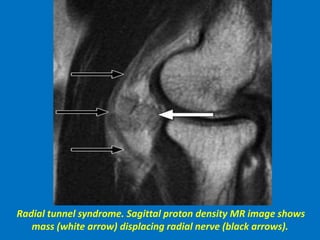

Radial tunnel syndrome. Sagittal proton density MR image shows

mass (white arrow) displacing radial nerve (black arrows).

The sagittal images confirm that this is a lipoma. Atrophy is a result of compression

of the posterior interosseous nerve, which is a branch of the radial nerve.